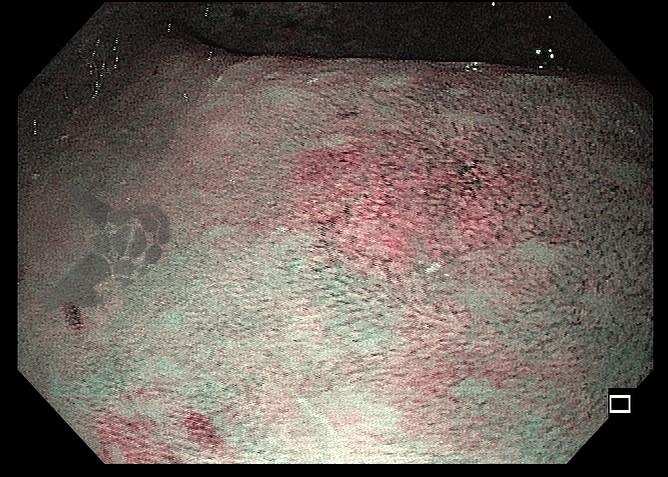

Paciente veio encaminhado para realizar nova colonoscopia na tentativa de ressecção completa da lesão. Durante o procedimento foi observada uma diminuta lesão amarelada no reto, discretamente elevada, correspondente à área de polipectomia prévia com presença de lesão residual (Figuras 1, 2 e 3). Realizada tentativa de mucosectomia pela técnica de imersão (“underwater”), não havendo pega adequada com a alça para ressecção. Foi optado, então, pela realização da mucosectomia por imersão assistida por cap, que consiste na imersão do espaço intraluminal com água, seguido por sucção da lesão com auxílio de cap endoscópico, afim de formar um pseudopólipo, e assim facilitar a apreensão e ressecção da lesão (Figura 4). Com o uso dessa técnica foi possível apreender a lesão residual com a alça e realizar sua ressecção completa (Figuras 5 e 6). O resultado anatomopatológico confirmou a presença de tumor neuroendócrino bem diferenciado (grau 1 – Ki67<2%), com margens laterais e profunda livres.